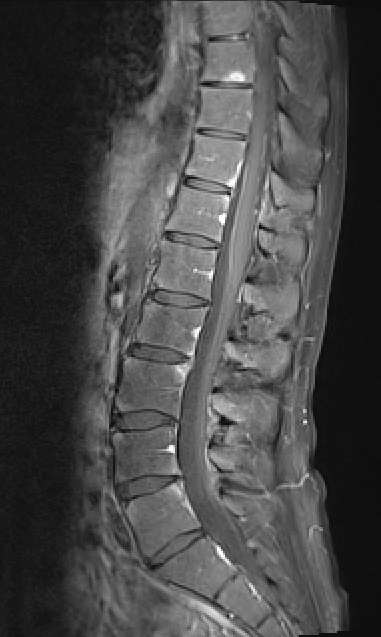

Allerdings zeigten sich schon recht bald nach dem Wechsel, dass 14 Tage dann wohl doch zu lange sind, um den Bechterew vollständig in Schach zu halten. Gegen Ende der jeweiligen Zeitphase bekomme ich neuerdings wieder die ganz klassischen Bechterew-Probleme im Hüftbereich. Die ich schon seit vielen Jahren nicht mehr hatte bzw. nicht mehr wahrgenommen habe, da die anderen durch die Entzündungen ausgelösten Probleme viel deutlicher und drängender waren. Nachdem diese aber ja in den vergangenen Monaten alle geheilt sind, merke ich nun den Beginn neuer Entzündungen recht deutlich. Und die treten dort zutage, wo die Bechterew-Entzündungen klassischer Weise nunmal meistens losgehen. Im Bereich der unteren LWS (Lendenwirbelsäule). Damit einhergehend oder eher dadurch begründet erlebe ich das als eine Art Flashback in längst vergangene und auch verdrängte Zeiten: ich wache gegen Ende der Nacht wieder früher auf, da es keine Position gibt, in der man noch beschwerdefrei liegen könnte. Meine Bewegungsfähigkeit ist die ersten Minuten nach dem Aufstehen wieder etwas eingeschränkt und ich habe meine Wärmflaschen wiederbelebt, da Wärme nach wie vor sehr gut gegen die Schmerzen hilft. Und ich komme mir allgemein ein Bisschen unbeweglicher vor als noch vor Wochen, das kann allerdings auch täuschen. Andererseits verflüchtigen sich all diese Probleme durch genügend Bewegung und ich musste (von einer Ausnahme abgesehen) auch nach wie vor nicht wieder zu Schmerzmitteln greifen. Dennoch: Im Körper passiert wieder etwas.